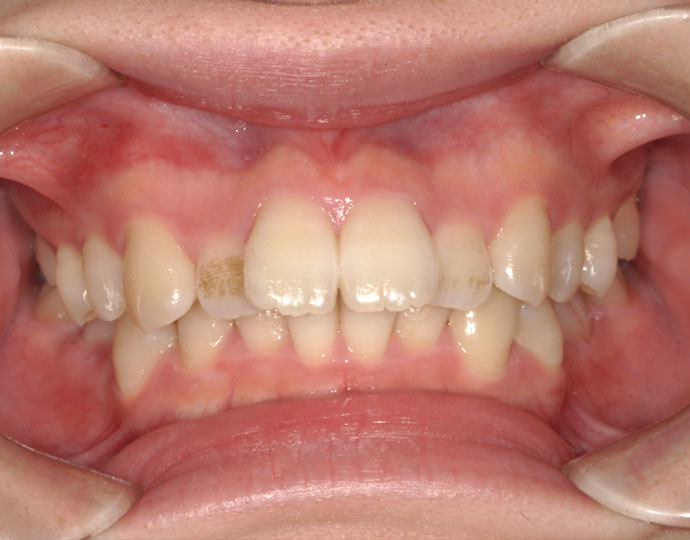

ワイヤー治療 叢生+上顎前突不正咬合 治療例

治療後

| 患者様 | 女性 19歳 |

| 主訴 | 歯並びと口元を綺麗にしたい。 |

| 診断 | 叢生歯列を伴う上顎前突不正咬合 |

| 治療方針 | 上顎左右第一小臼歯、下顎左右第二小臼歯の抜歯 |

| 治療に使用した装置 | セルフライゲーションブラケット インプラントアンカースクリュー×2 |

| 治療期間 | 2年6カ月 |

| 治療回数 | 24回 |

| 治療費(自費診療) | 880,000円(税込み) |